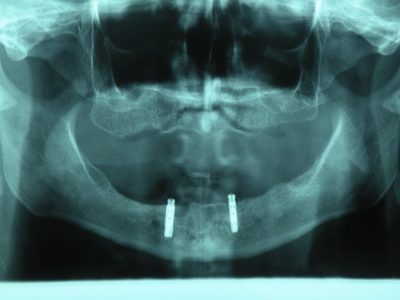

Implantat je zapravo zamjena za korijen zuba. Riječ je o vijku točno određene veličine koji se ugrađuje u kost čeljusti. On je izrađen od titana, plemenitog materijala, jedinog kompatibilnog sa ljudskom kosti. Odluka o postavljanju implantata donosi se na temelju digitalnog ortopana i kompjuterizirane tomografije (CT-a), odnosno snimke čeljusti. Implantologijom se može nadomjestiti jedan ili više zuba, a implantat je temelj, ili bolje rečeno, nosač za protetske nadomjestke. Na implantate možemo pričvrstiti proteze i mostove, ali jedan implantat može nadomjestiti i samo jedan zub ukoliko samo jedan zub manjka u zubnom nizu.